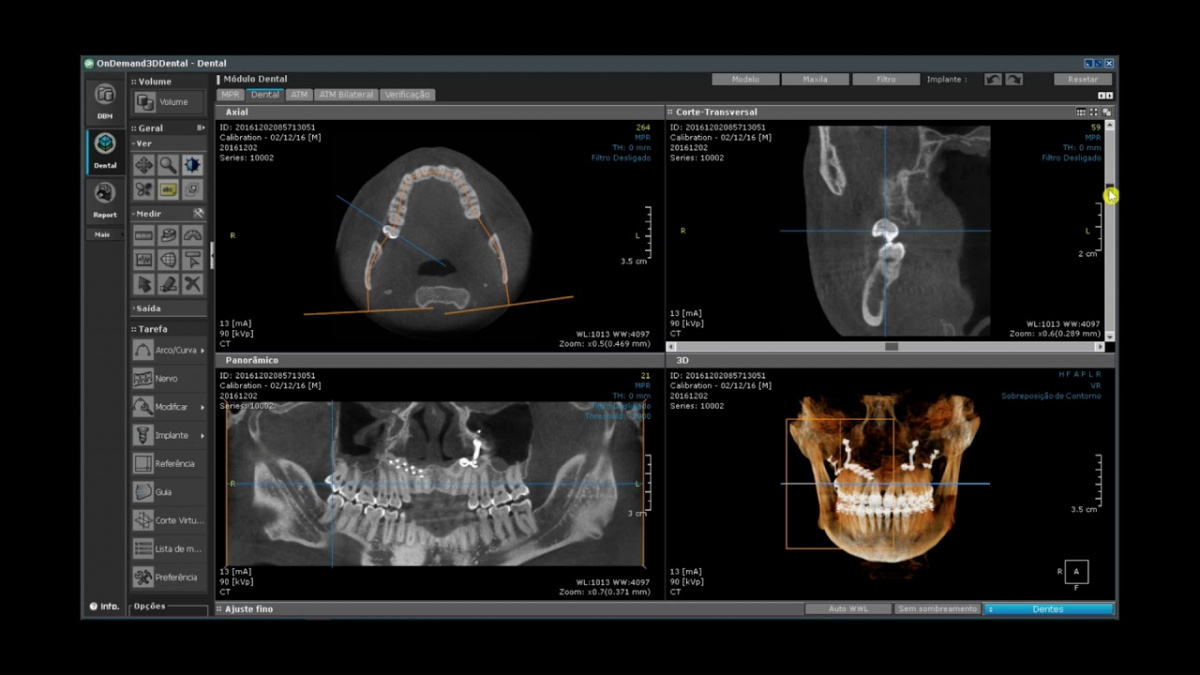

Немаловажным, а может главным вопросом, является универсальность программы-просмотровщика, в которой будут работать врачи-стоматологи. У Papaya 3D есть два варианта программ: Triana и OnDemand3D. Оба просмотровщика обладают схожим интерфейсом и имеют самые важные опции, а именно:

Таким образом обе программы являются простыми в пользовании, но обладающими обширным спектром возможностей для диагностики любыми специалистами-стоматологами. В данные программы происходит загрузка классических файлов DICOM 3.0, которые являются общепринятым форматом записи данных пациента. Это важный момент, так как позволяют врачу, имеющему полную версию программы загружать даже сторонние исследования и просматривать их в этих программах. Простота в освоении этих программ позволяет даже специалисту, не работающему раннее с этими программами, быстро адаптироваться и получить качественную информацию. Возможность выгрузки STL-файла дополнительно создает возможность интегрировать данные с цифровым ортопедическим протоколом.

Как правило, многие томографы комплектуются отдельно без специализированного компьютера, который анализирует и выводит изображение. У него должен быть высокотехнологичный процессор и видеокарта, что сразу удорожает приобретение аппарата. При покупке Papaya 3D такой компьютер уже входит в стоимость, что позволяет снизить расходы клиники. Также, Papaya 3D, обладает функцией по уменьшению артефактов от различных металлических конструкций. Вообще артефакты являются главной проблемой многих КТ, поэтому полностью ее устранить пока не удается. Однако благодаря технологии SMARF у Papaya 3D качество снимков отличается меньшим воздействием артефактов. А это особенно необходимо при анализе исследований врачом-терапевтом, ортопедом и др.